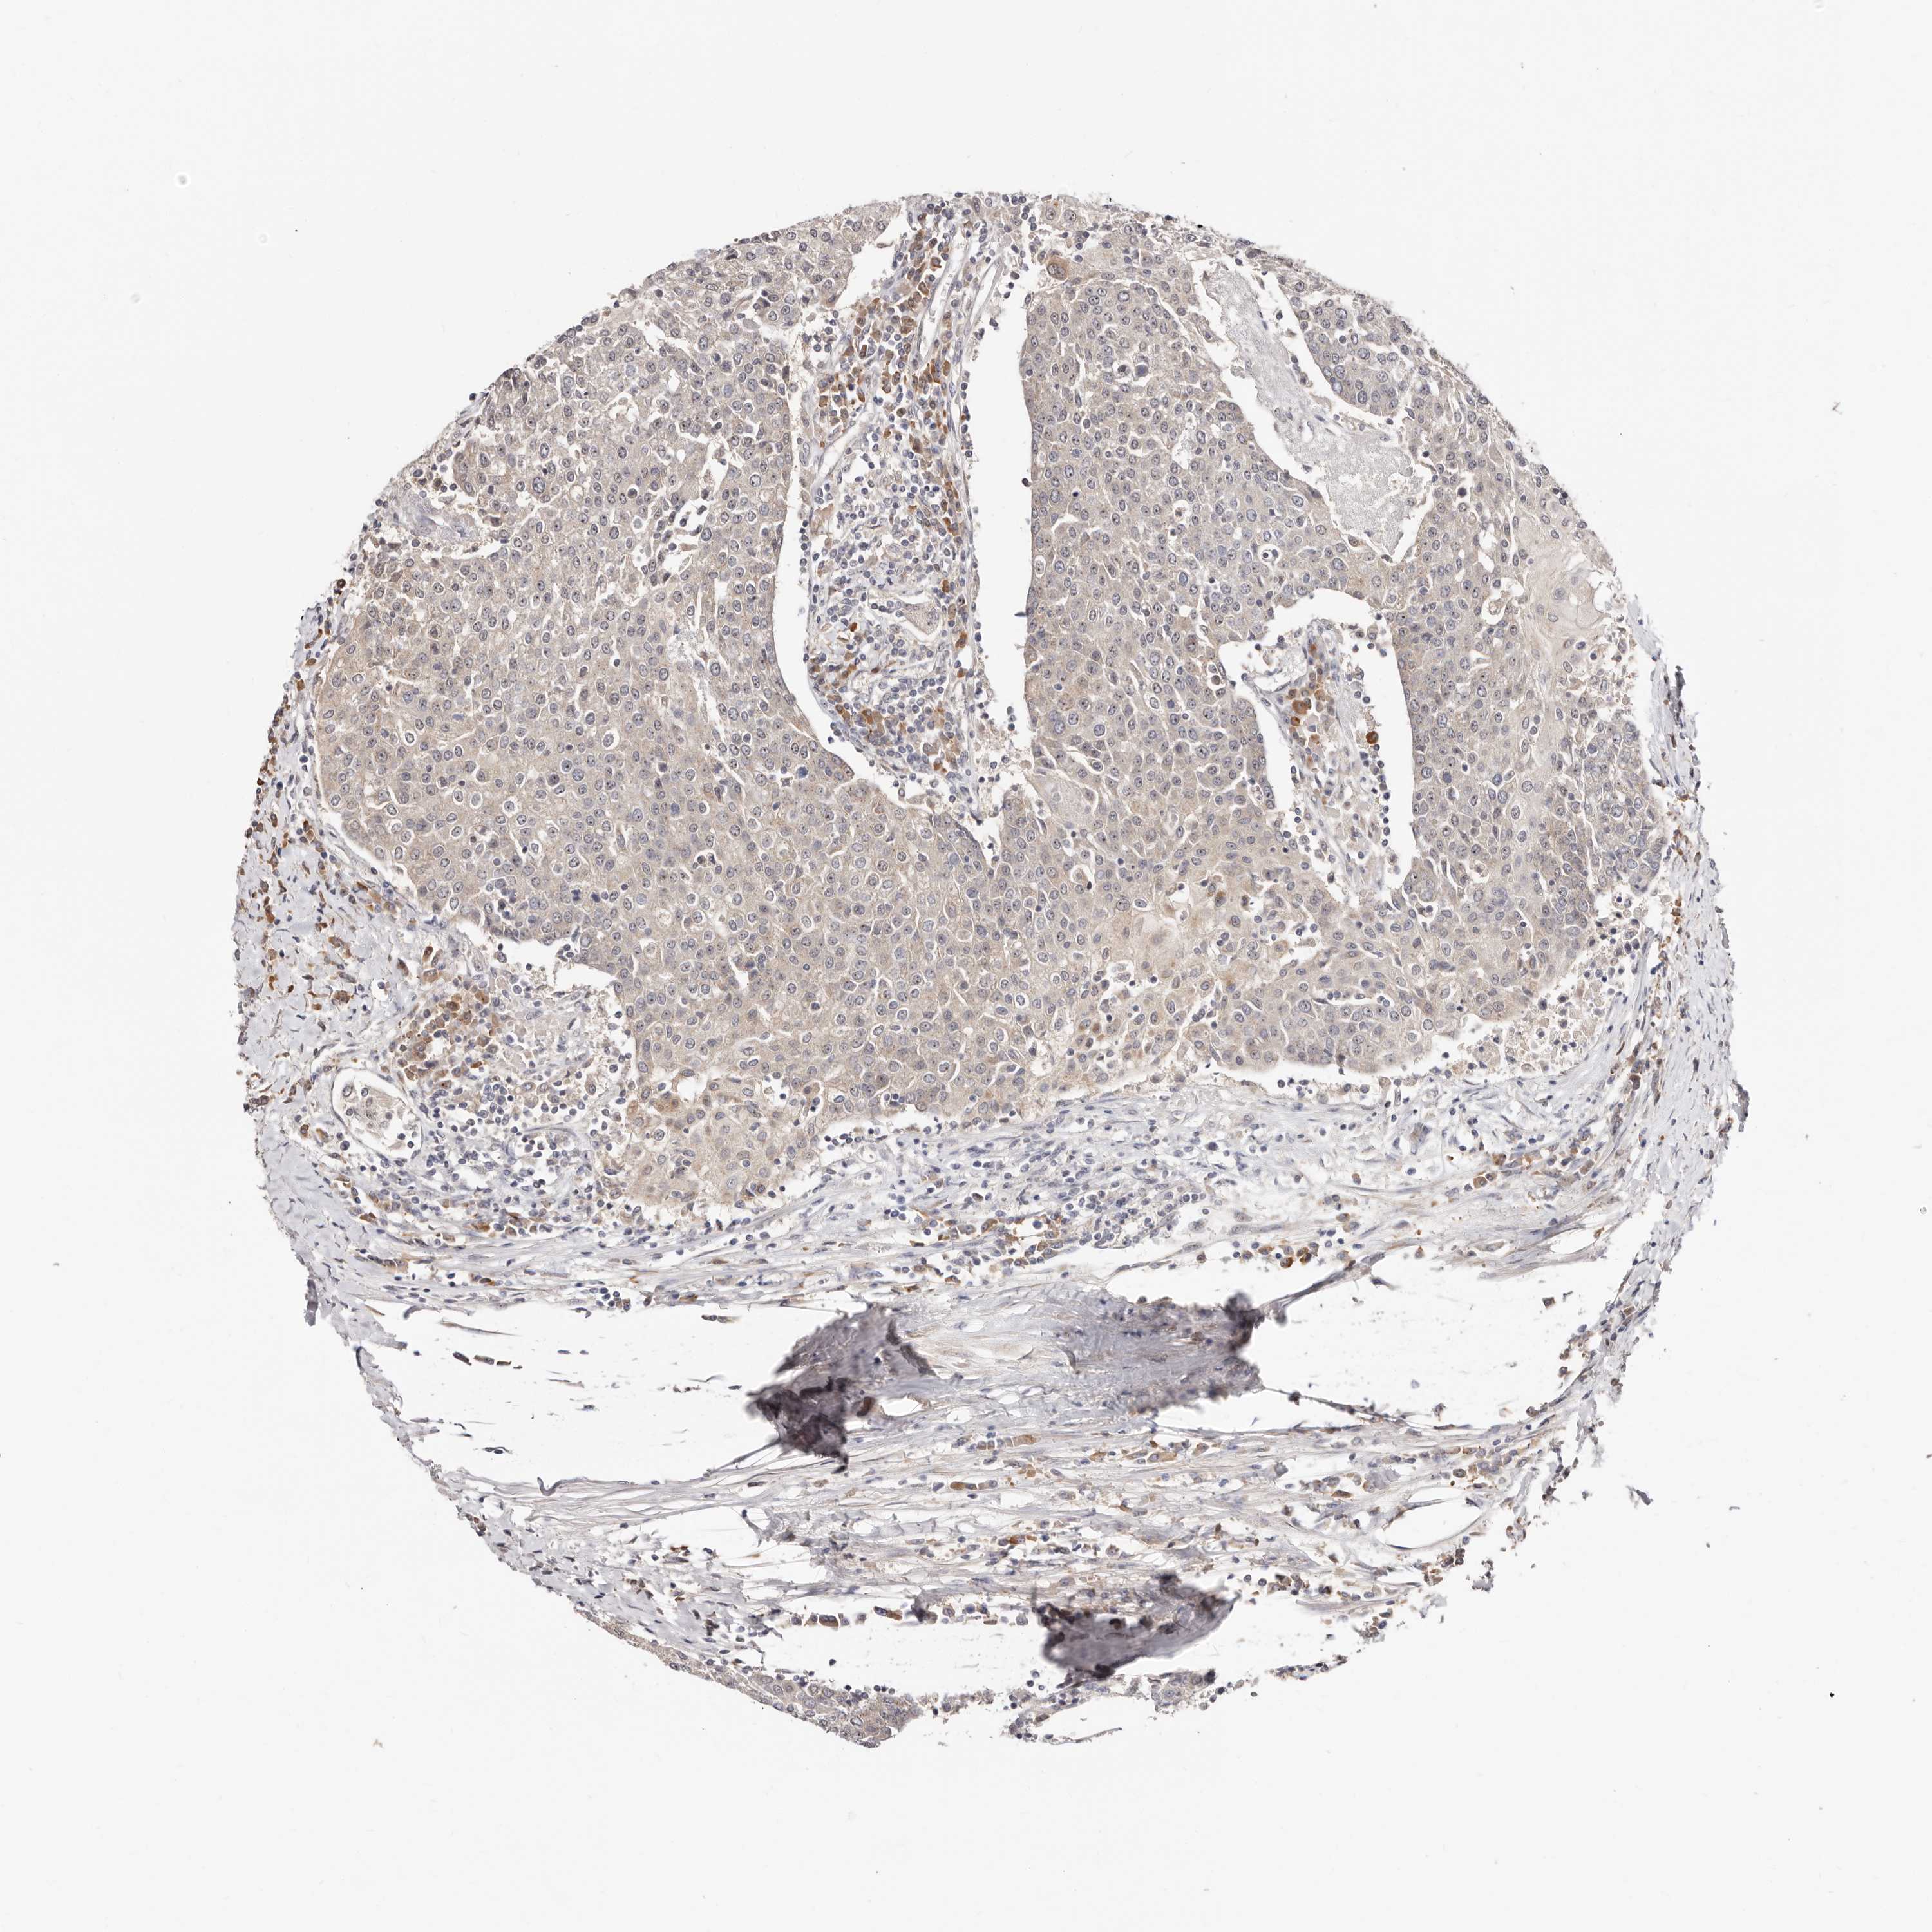

UROTHELIAL CANCER - Protein expressioni

A mouse-over function shows sample information and annotation data. Click on an image to view it in a full screen mode. Samples can be filtered based on level of antibody staining by selecting one or several of the following categories: high, medium, low and not detected. The assay and annotation is described here.

Note that samples used for immunohistochemistry by the Human Protein Atlas do not correspond to samples in the TCGA dataset.

Antibody stainingi

Antibody staining in the annotated cell types in the current human tissue is reported as not detected, low, medium, or high, based on conventional immunohistochemistry profiling in selected tissues. This score is based on the combination of the staining intensity and fraction of stained cells.

Each image is clickable and will lead to virtual microscopy that enables deeper exploration of all samples and also displays staining intensity scores, fraction scores and subcellular localization as well as patient and tissue information for each sample.

Antibody HPA029165

Antibody HPA029167

Antibody CAB028574

Staining

High

Medium

Low

Not detected

Intensity

Strong

Moderate

Weak

Negative

Quantity

>75%

75%-25%

<25%

None

Location

Nuclear

Cytoplasmic/membranous

Cytoplasmic/membranous,nuclear

Urothelial carcinoma, Low grade

Urothelial carcinoma, High grade